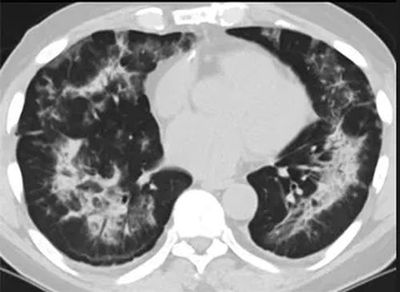

(这4张图,是专家怀疑被误诊为电子烟肺病的其中一个病例的肺片。专家表示,他们不是仅仅通过一张影片做判断的,而是通过这4张涵盖了这名病例肺部多天变化情况的影片进行的研判,认为该病例的病程进展跟新冠更为相似)